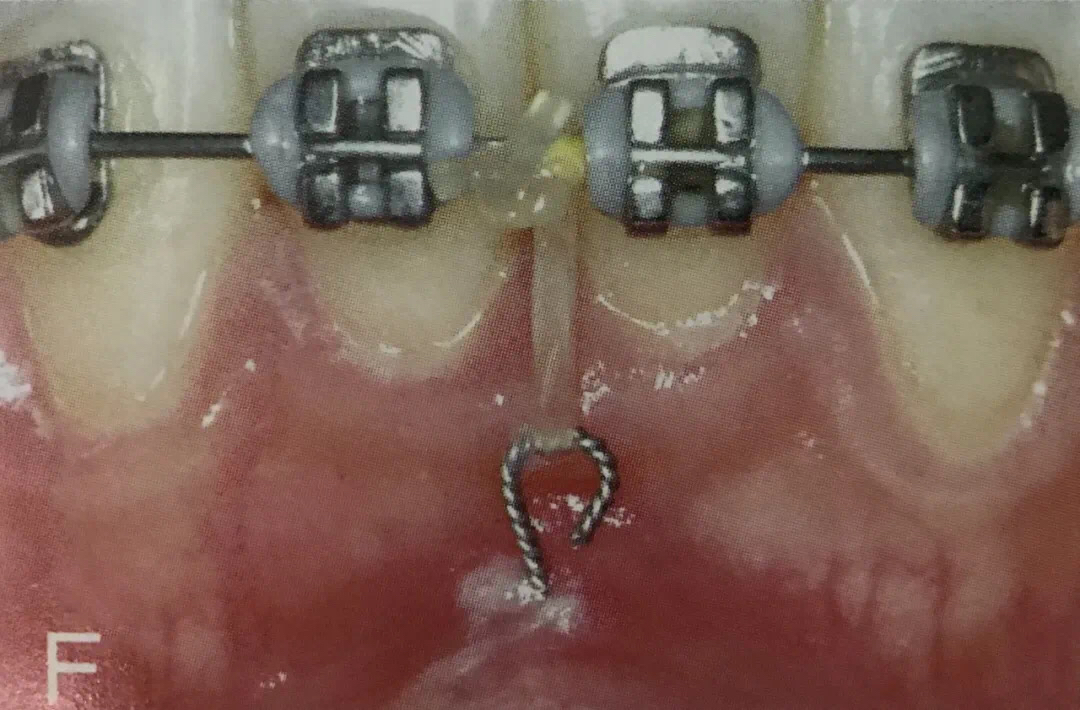

3. 压低前牙

露龈笑患者需要利用支抗钉压低上前牙、缩短牙龈高度;深覆合患者需要支抗钉压低上前牙,减小深覆合程度,防止咬合加深。

反颌患者需要利用支抗钉压低下前牙,减小反覆合,改善“地包天”。